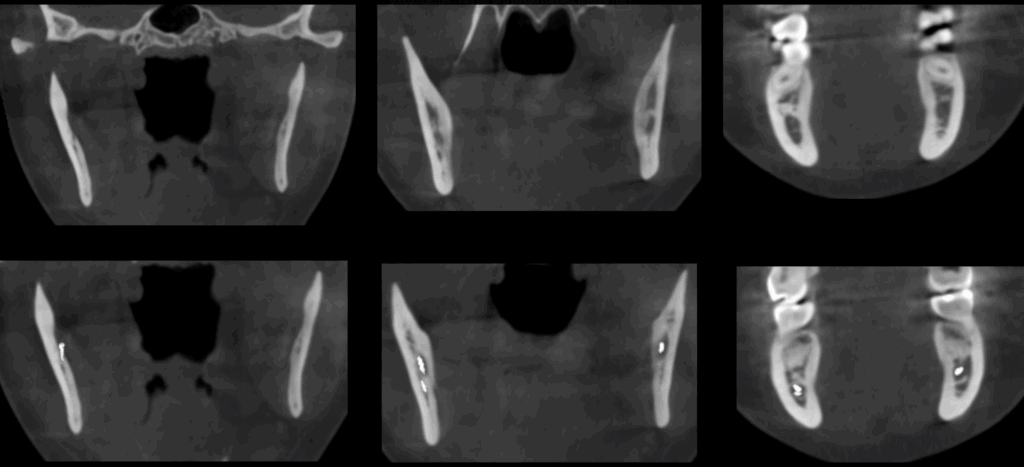

A la evaluación de la tomografía de cráneo completo se encontró un hallazgo imagenológico en el cuarto cuadrante, se observó la bifurcación del conducto dentario inferior que iba desde su entrada por el agujero mandibular y se orienta caudal al conducto dentario principal para volver a unirse con el mismo a nivel apical de la primera molar.

CORTES CORONALES